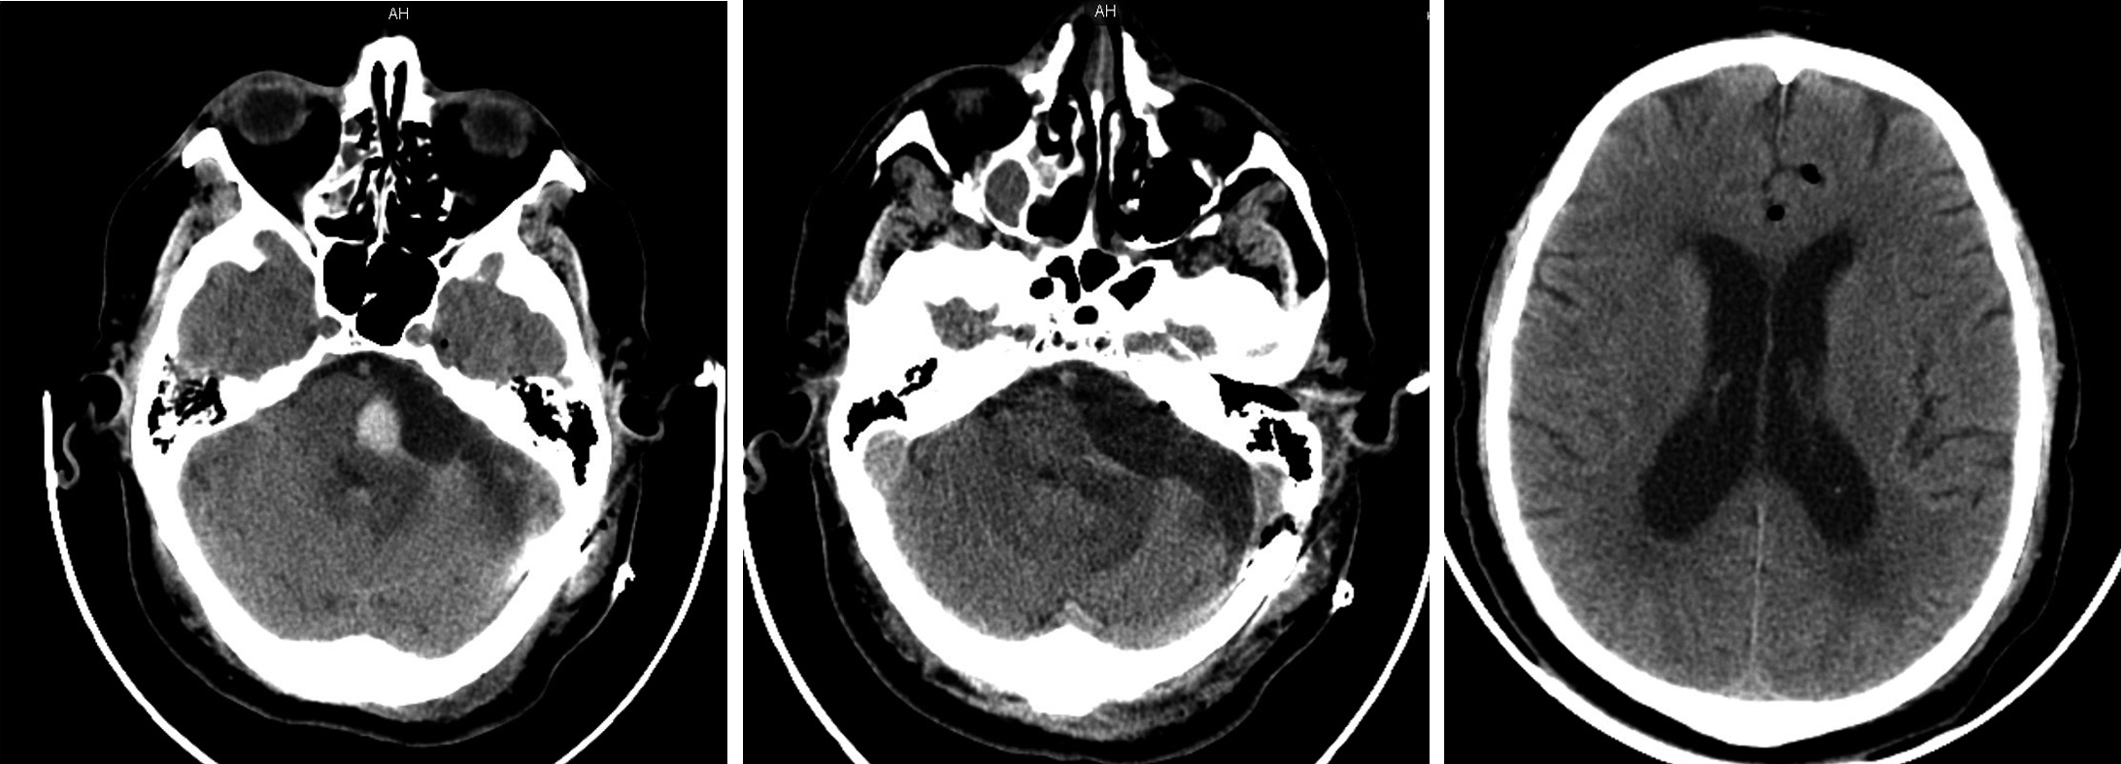

The patient has been experiencing a gradual decrease in hearing in the left ear for 2 years. In 2018, the patient's condition worsened: headache, unsteady gait, dizziness, lacrimation from the left eye, and complete deafness in the left ear developed. Magnetic resonance imaging (MRI scan) of the brain revealed the following: a VS up to 4.6 cm on the left (Fig. 1); severe compression of the pons and the left cerebellar hemisphere; compression and displacement of the fourth cerebellar ventricle; and communicating triventricular hydrocephalus without periventricular edema or girus flattening.

Fig. 1. Preoperative brain MRI of the patient revealed a left cerebellopontine angle tumor with intense inhomogeneous accumulation of paramagnetic contrast agent. Lateral ventricles are dilated. Preoperative coronal and axial contrast-enhanced T1-weighted MR images.